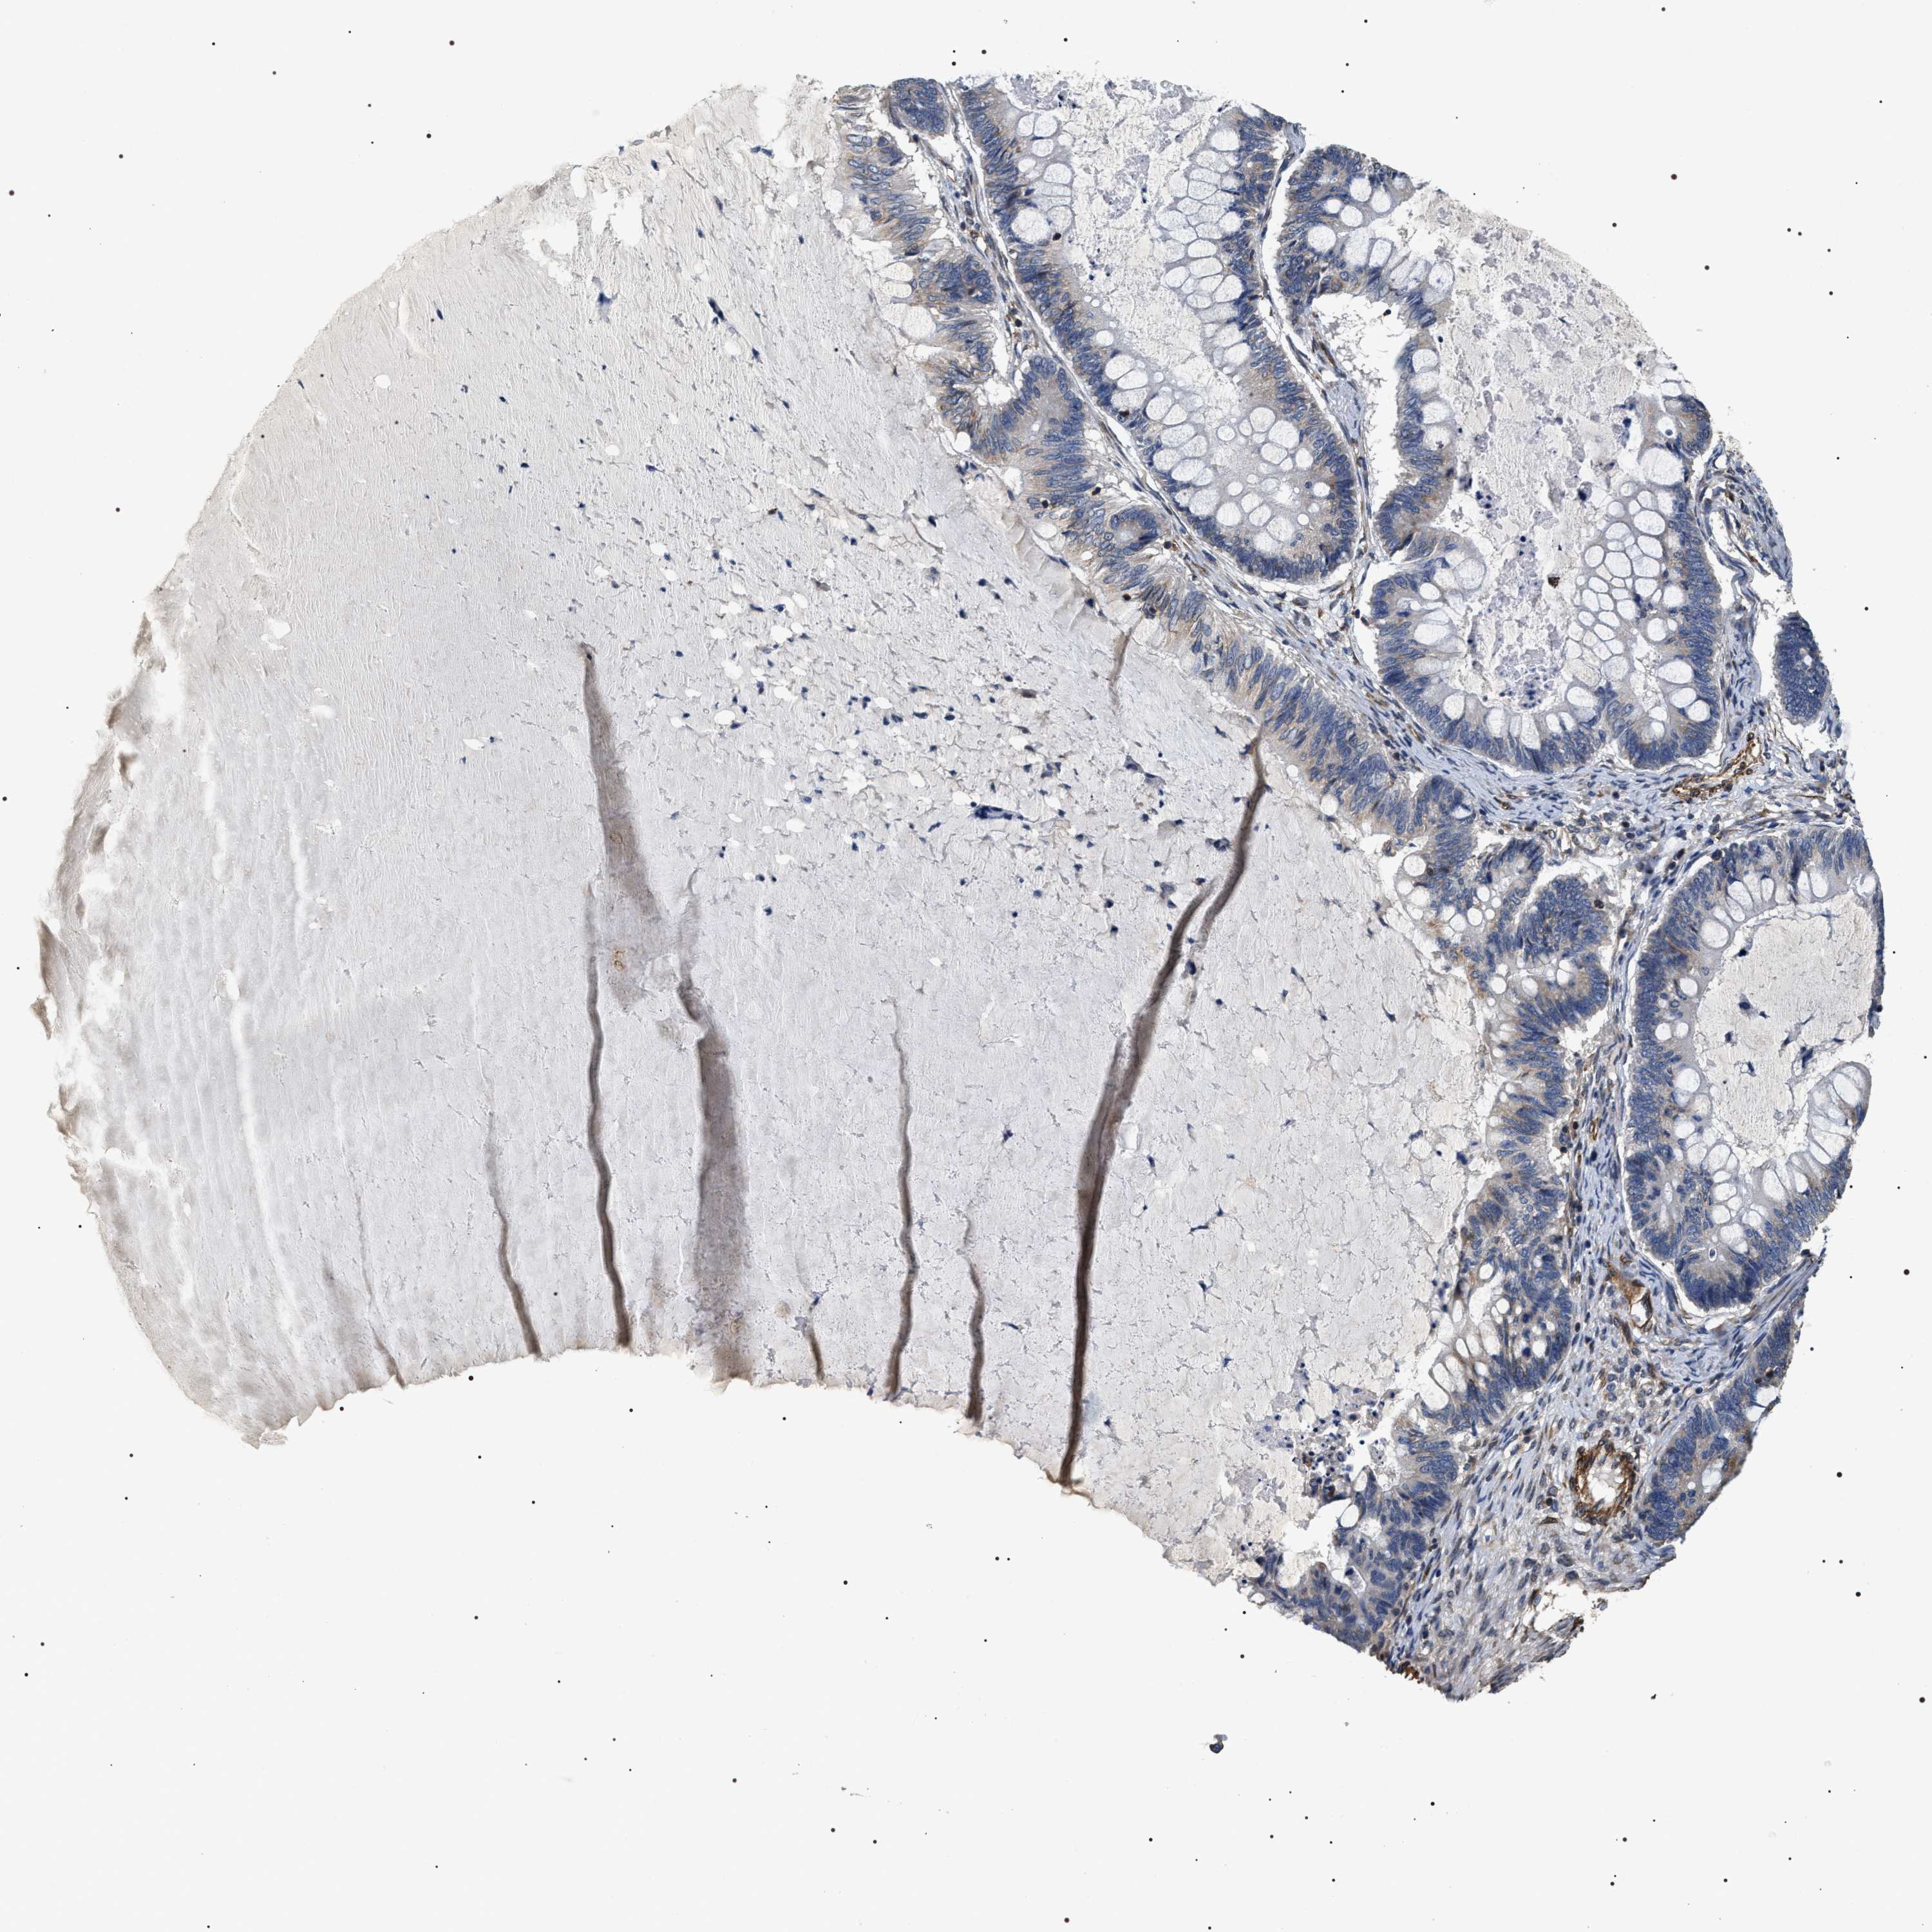

OVARIAN CANCER - Protein expressioni

A mouse-over function shows sample information and annotation data. Click on an image to view it in a full screen mode. Samples can be filtered based on level of antibody staining by selecting one or several of the following categories: high, medium, low and not detected. The assay and annotation is described here.

Note that samples used for immunohistochemistry by the Human Protein Atlas do not correspond to samples in the TCGA dataset.

Antibody stainingi

Antibody staining in the annotated cell types in the current human tissue is reported as not detected, low, medium, or high, based on conventional immunohistochemistry profiling in selected tissues. This score is based on the combination of the staining intensity and fraction of stained cells.

Each image is clickable and will lead to virtual microscopy that enables deeper exploration of all samples and also displays staining intensity scores, fraction scores and subcellular localization as well as patient and tissue information for each sample.

Antibody HPA020386

Staining

High

Medium

Low

Not detected

Intensity

Strong

Moderate

Weak

Negative

Quantity

>75%

75%-25%

<25%

None

Location

Nuclear

Cytoplasmic/membranous

Cytoplasmic/membranous,nuclear

Cystadenocarcinoma, serous, NOS

Carcinoma, endometroid

Cystadenocarcinoma, mucinous, NOS

Carcinoma, NOS